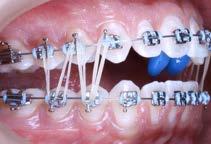

Se describe un caso de un paciente masculino de 18 años de edad, con diagnóstico de clase II esquelética, normodivergente, clase II canina y molar bilateral, overjet aumentado, laterales microdónticos, apiñamiento leve superior e inferior, asimetría facial, canteamiento oclusal y con hábito de deglución atípica. Objetivos: mejorar el perfil facial, corrección del apiñamiento maxilar y mandibular, del overjet y overbite y de las líneas medias dentales, así como la obtención de clase I molar y canina bilateral. Generar remodelación condilar a largo plazo, corrección de hábito, lograr correcta intercuspidación, lograr guía de desoclusión canina, lograr guía incisiva, gingivectomía, exodoncias de terceros molares 18, 28, 38 y 48 y restauración de incisivos superiores 11, 12, 21 y 22. Tratamiento: alineación, nivelación, avance mandibular, stripping, detallado y retención. A través de brackets prescripción Roth 0.022 x 0.028”, tubos bondeables en primeros y segundos molares y bite ramps angulados en incisivos centrales superiores 11 y 21. El tiempo activo de tratamiento fue de 1 año y 4 meses, la retención se llevó a cabo mediante retenedores circunferenciales con cinturón vestibular en ambas arcadas y un Frankel unilateral izquierdo de uso nocturno.

El tratamiento consistio en alineación, nivelación, avance mandibular, stripping, detallado y retención. La corrección del apiñamiento maxilar y mandibular se resolvió a través de

alineación y nivelación haciendo uso de la técnica de bondeado indirecto (Figura 9 y 16) con secuencia de arcos CuNiTi 0.016” superior, NiTi 0.016, 0.016” x 0.022”, 0.017” x 0. 025” y acero inoxidable 0.018”.

La obtención de clase I canina y molar bilateral se obtuvo mediante el avance mandibular y uso de elásticos intermaxilares con el uso de bite ramps en 11 y 21 angulados largos, elásticos clase II cortos y largos de 3/16” 4.5 oz sencillos y dobles figura 10 y elásticos clase II continuos en W de uso nocturno de 5/16” 2.5 oz (Figura 1). La corrección del overjet y overbite se alcanzó con anclaje mínimo, elásticos intramaxilares, IPR, rebondeo y arcos seccionales mediante ferulizado con ligadura metálica de segundo molar superior derecho 17 a canino superior derecho 13 y de lado contrario de 27 a 23, tie back inferior, stripping de 33 a 43, cadena de canino a canino superior de 13 a 23 y de primer molar a primer molar inferior de 36 a 46, “Storino Leash" anteroinferior de 33 a 43, rebondeo con alturas Pitts en anterosuperior y arcos seccionales de NiTi 0.016”. Máxima intercuspidación, paralelismo radicular y